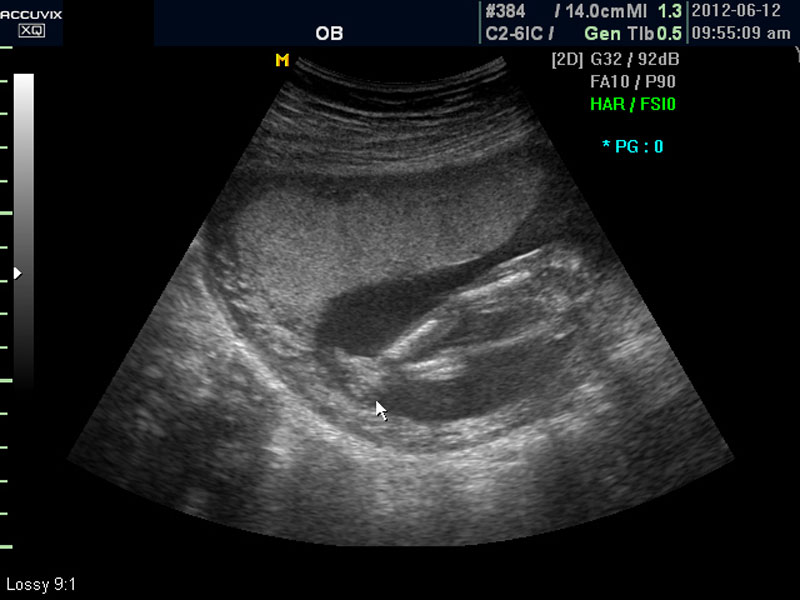

위 사진은 태아의 발바닥 사진인데 사진에서 보는 것처럼 그러나 이 시기는 손가락이나 발가락 또는  심장 내부의 구성 이상 등의 세세한 부분은 아직 크기가 작아서 제대로 확인하기 어려운 시기입니다.

대신 첫번째 사진에서 보는 것처럼 태아의 전체 모습 특히 태아의 등쪽이나 복벽의 이상은 없는지 신경관 결손 등으로 인한 종괴가 있지는 않은지 관찰하며 태아의 복벽이나 등쪽은 일직선으로 매끈하게 보이는 것이 정상입니다.

첫번째 사진에서는 하지 부분은 대퇴부만 일부 보이며 이는 태아가 다리를 구부리고 있고 팔도 이리저리 움직여 머리 위나 목 쪽으로 두는 경우가 많아서 한번에 전체 모습을 찍기가 어려운 경우가 많습니다.

따라서 부분 부분 살펴 보면서 해당 모습을 찍어서 저장하거나 인쇄하여 드리기도 하는 것이며 아래 사진은 태아의 다리 부분을 찍은 것입니다.

화면에서는 위쪽에 하얗게 균일하게 보이는 것이 태반의 모습입니다.

태반은 실제로 보면 피자처럼 둥그런 원판 모양이며 임신 후기로 갈수록 태아와 마찬가지로 크기가 커지고 두꺼워집니다.

양수의 양은 태아의 건강과 관련된 지표로 너무 많거나 너무 적으면 좋지 않은데 그 절대양을 측정할 수는 없어서 양수가 많은 부분의 깊이를 측정하거나 혹은 개략적으로 전체에서 차지하는 부분을 봐서 이상 여부를 판단합니다.

사진에서 검게 보이는 것이 양수입니다. 양수에 대하여는 색깔이나 밀도 등 다른 요소는 알기 어려워서 그 양만 가지고 판단을 하게 됩니다.